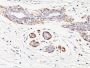

IHC, FFPE (verified)

Smooth muscle myosin heavy chain (SM-MHC) is a cytoplasmic structural protein, which is a major component of the contractile apparatus in smooth muscle cells. Expression of smooth muscle myosin is developmentally regulated, appearing early in smooth muscle development, and is specific for smooth muscle development. Two isoforms of smooth muscle myosin heavy chain have been identified, designated MHC-1 and MHC-2. The antibody may be useful for the study of breast tumors as the presence of an intact layer of myoepithelial cells is an important feature, which may distinguish benign breast lesions and carcinoma in situ from invasive tumors.Primary antibodies are available purified, or with a selection of fluorescent CF® Dyes and other labels. CF® Dyes offer exceptional brightness and photostability. Note: Conjugates of blue fluorescent dyes like CF®405S and CF®405M are not recommended for detecting low abundance targets, because blue dyes have lower fluorescence and can give higher non-specific background than other dye colors.

Uterus or normal breast

Higher concentration may be required for direct detection using primary antibody conjugates than for indirect detection with secondary antibody|Immunofluorescence: 0.5-1 ug/mL|Immunohistology formalin-fixed 0.5-1 ug/mL|Staining of formalin-fixed tissues requires boiling tissue sections in 10 mM citrate buffer, pH 6.0, for 10-20 min followed by cooling at RT for 20 minutes|Flow Cytometry 0.5-1 ug/million cells/0.1 mL|Predicted to show broad species reactivity|Optimal dilution for a specific application should be determined by user